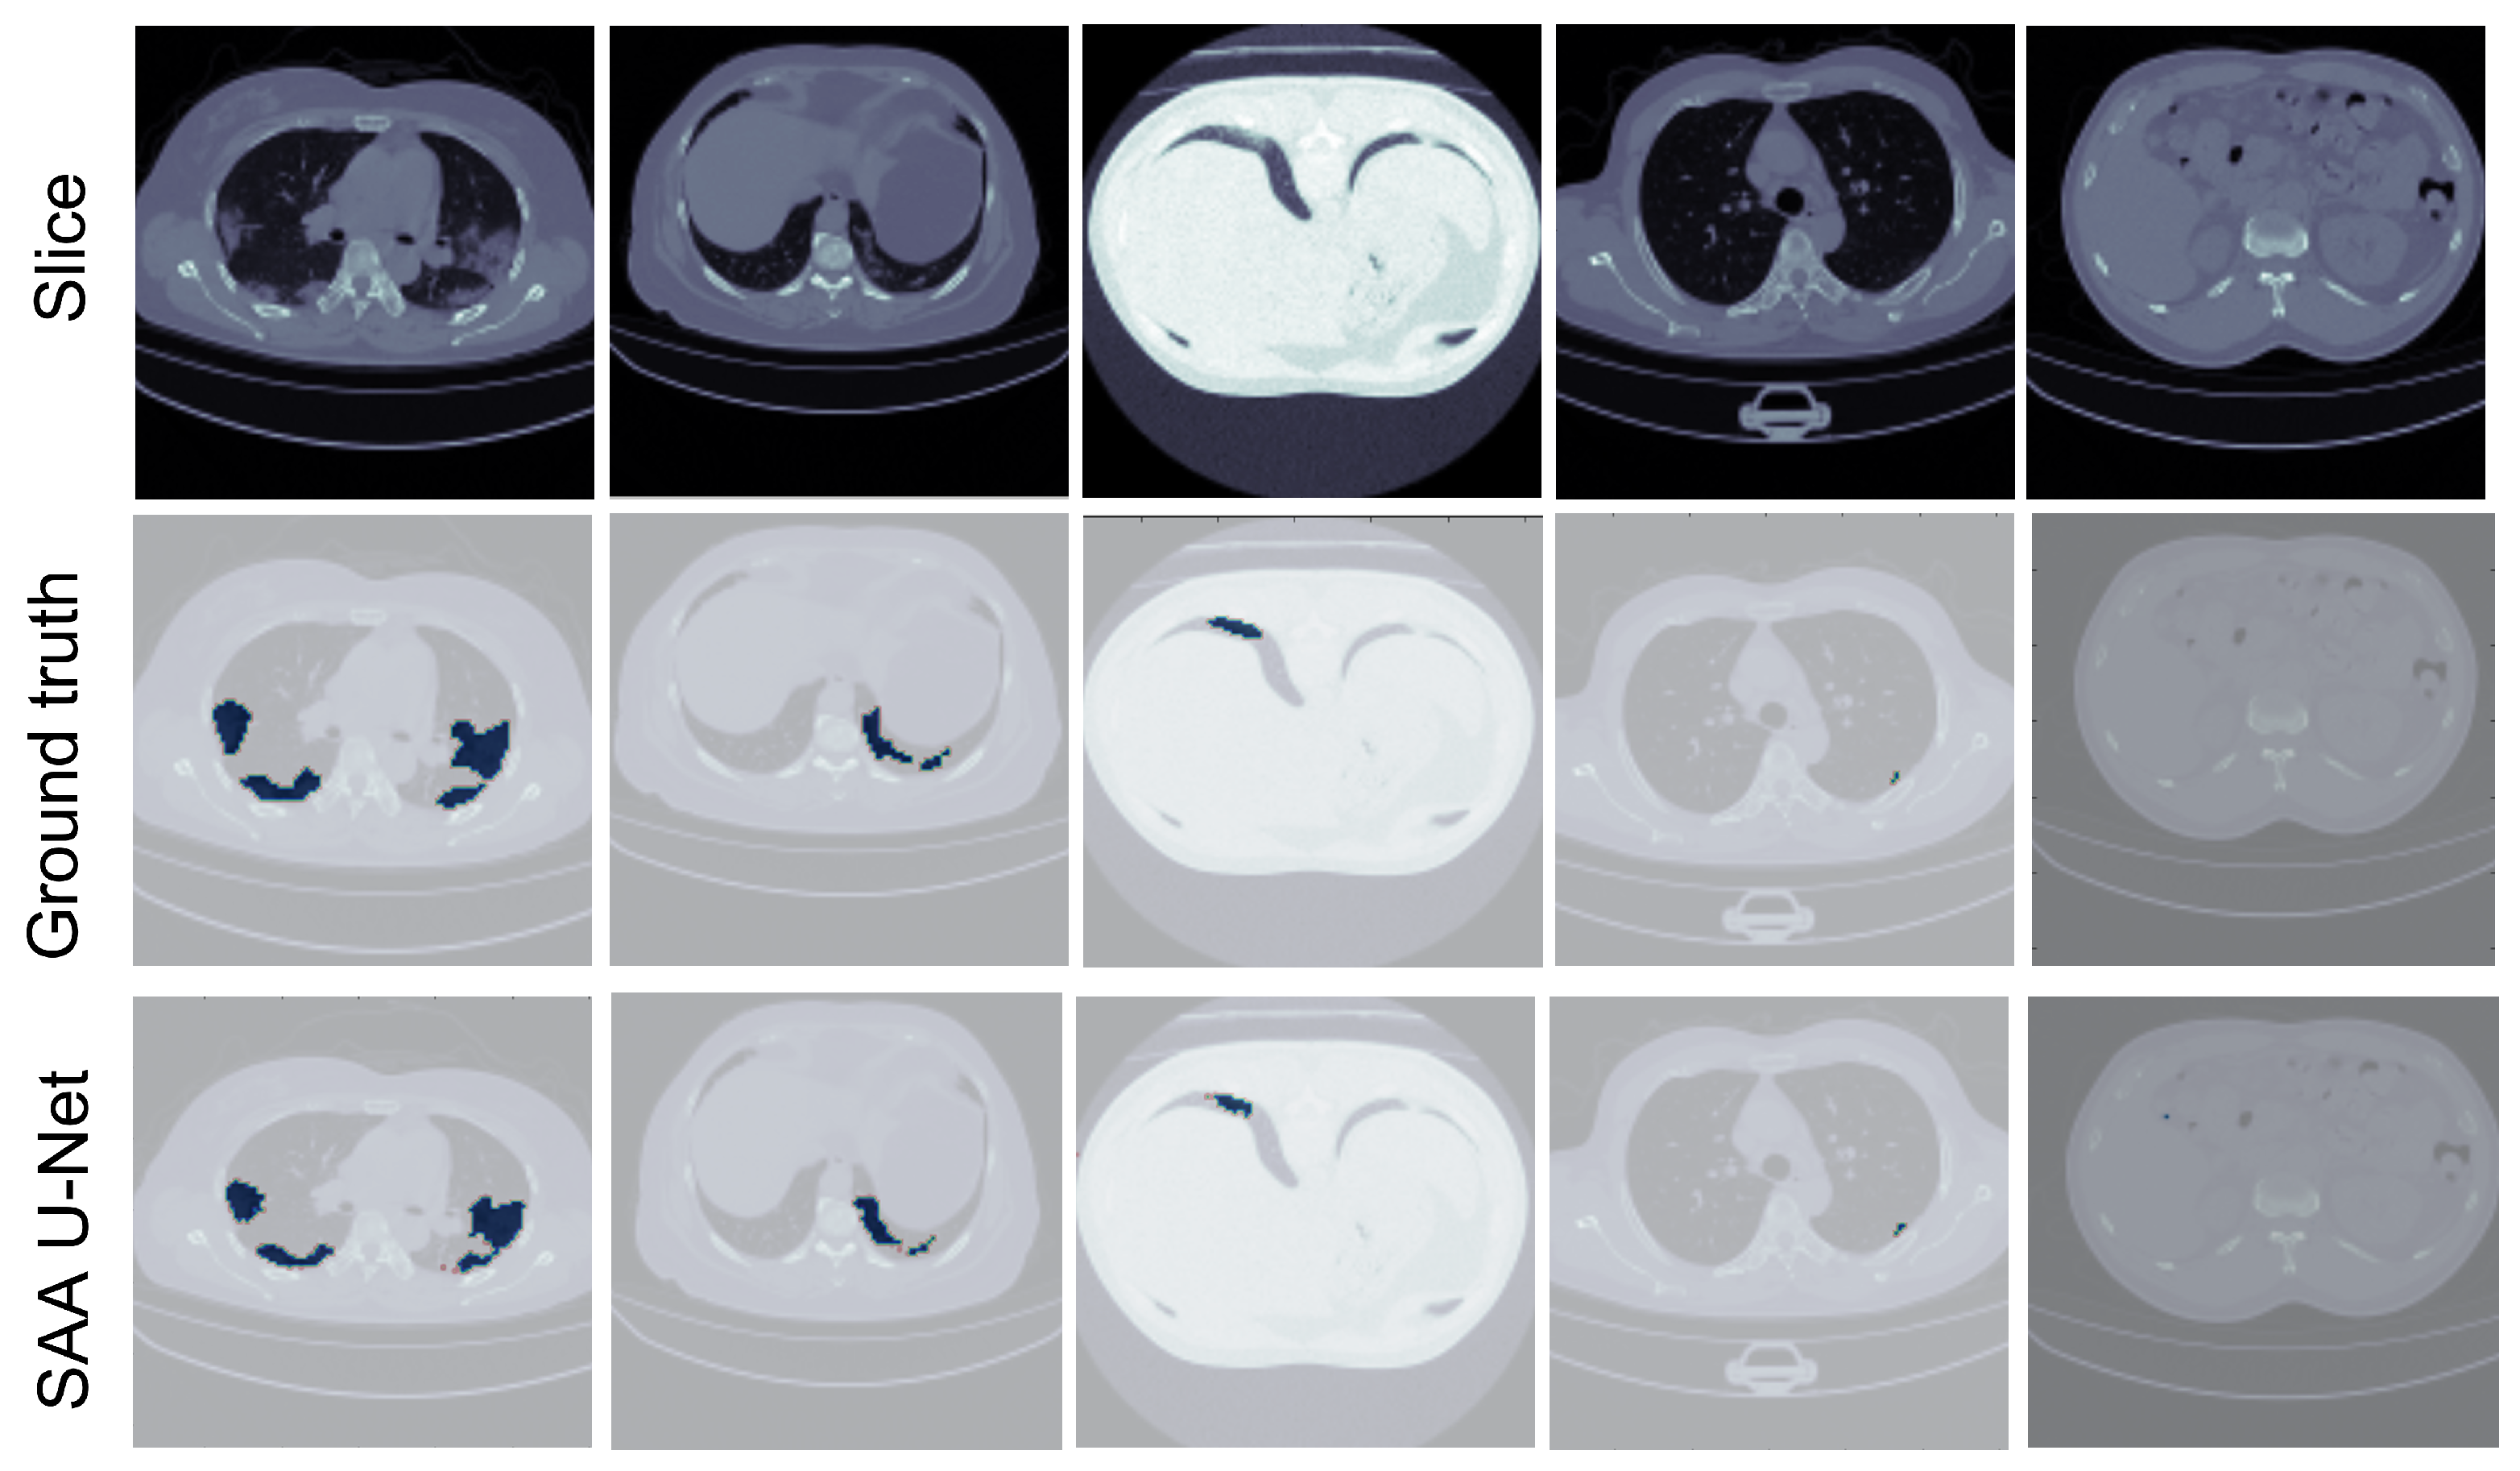

Figure 11 illustrates that the SAA-UNet model can predict different sizes and shapes of the infection. Likewise, SAA-UNet can detect if there is no infection in the CT slices with a mean Dice score of 0.99. As a result, SAA-UNet can diagnose and detect the infection effectively even at the beginning of the appearance of pneumonia in the patient’s lung.

Figure 11.

The predicted CT slices for COVID-19 infection with different sizes. The blue color is for infection, and the others are for the background.